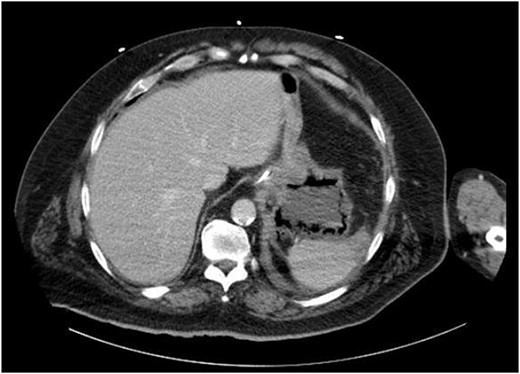

The decision was made to take the patient to the operating room. He underwent diagnostic laparoscopy, which showed a normal gastric antrum; however, on further inspection, a hemorrhagic and inflamed area of stomach was seen proximally at the fundus on the underside of the diaphragm. Next, esophagogastroduodenoscopy was performed, which demonstrated a large black necrotic area in the fundus (Fig. 3), as well as inflammation throughout the rest of the gastric body (Figs 4 and 5). At this point, malignancy could not be ruled out, so the operation was converted to open with a subxiphoid to supraumbilical midline incision. Once in the abdomen and able to further inspect the stomach, the frankly necrotic portion of fundus was noted to be adhered to the underside of the diaphragm and a contained purulent fluid collection was encountered in this area and drained. A partial gastrectomy was then undertaken in similar fashion to a sleeve gastrectomy. The lesser sac was entered and the stomach mobilized along the greater curvature with an energy device up through the short gastrics. A stapler was used to resect the entire necrotic portion of stomach from the midbody to the angle of His. Frozen sections were sent which were negative for malignancy. The remaining stomach was inspected for signs of malignancy, but none were found. For these reasons, no further resection was done. The entire staple line was imbricated due to concern for an ischemic etiology for the patient’s disease process, and two drains were left—one anterior and one posterior to the staple line. Final pathology showed prominent gangrenous necrosis, ulcer and acute necro-inflammatory exudate. Most of the specimen had no viable gastric mucosa, and no malignancy was found.